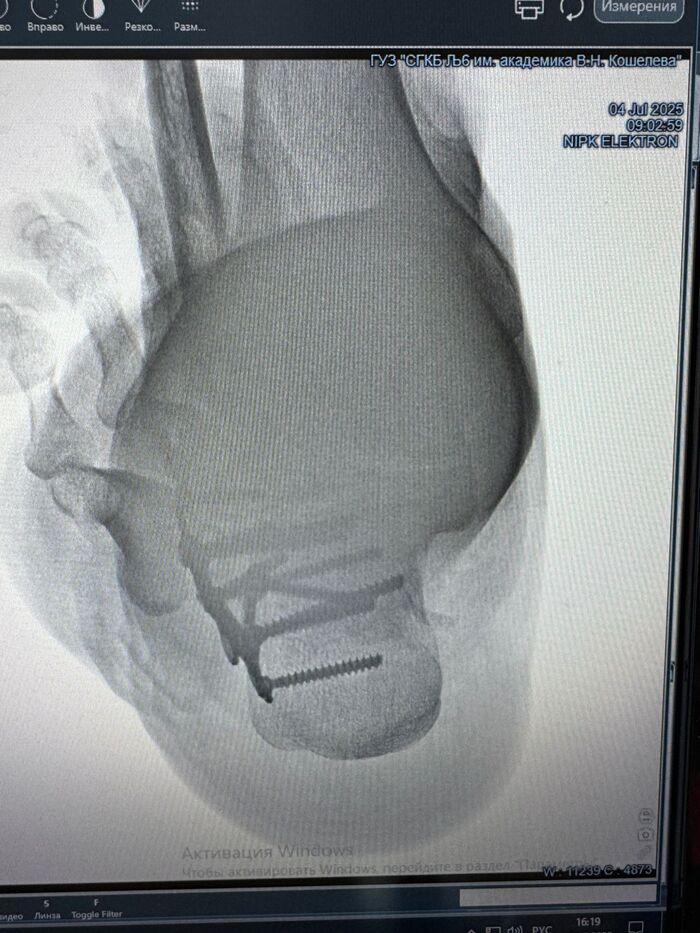

В итоге знакомые порекомендовали хорошего хирурга-травматолога, мне разломали пятку (осколки местами кое-где срослись углами), зашили в ногу титановую пластину и к ней винтами прикрутили осколки пяточной кости. А через полгода-год опять надо будет ногу резать, чтоб пластину извлечь.

Нога моя, титановая пластина теперь тоже моя)